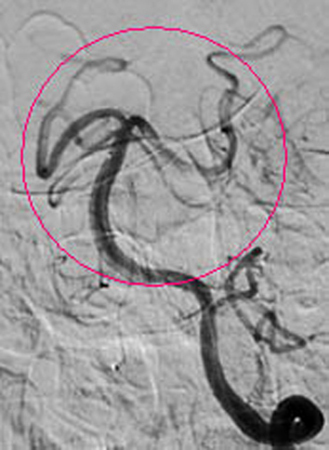

红圈内血管完全闭塞

红圈内所示为经动脉接触溶栓后,血管再通。 7月21日上午,在我院神经外科医护人员的团结协作下,成功完成一例急性脑梗塞介入动脉溶栓手术,该项手术的成功开展,使我院急性溶栓技术达到了新的高度,为全市人民带来福音。 患者张大妈,今年77岁,因“晨起洗脸时突发昏迷1个小时”急诊送入我院,行头颅CT示:排除脑出血、脑梗塞可能。神经外一科9:40接急诊内科紧急会诊通知,王和平医生9:45赶到急诊内科,在了解了病人的一般情况后,考虑患者来院比较及时,还在动脉溶栓时间窗内,遂急诊介入行全脑血管造影,明确为基底动脉完全闭塞(此病致死率高达90%),继而予尿激酶行基底动脉内接触溶栓!之后行造影明确,基底动脉通畅、显影(造影图片见后)!当天下午,患者神志基本清醒,竟然向医生提出要求:要求回家给儿孙做饭。 急性脑梗塞,超早期(起病3小时内)的静脉溶栓治疗是传统的药物治疗,称为“黄金三小时”。但绝大多数患者在该时间段内来不到医院,或是到了医院还来不及明确诊断。但动脉溶栓可将该时间段延长至6-8小时(前循环),后循环血管闭塞甚至可延长到24小时。并且,动脉溶栓目的性更强(直接将溶栓药物灌注在血栓上),全身副反应更小,效果更好。这样就为本类患者的救治提供了机会! 随着2012年我院成为国家卫计委的脑卒中筛查与防治基地,我院对脑卒中的诊断与治疗水平有了进一步的提高。尤其是2013年新型飞利浦数字血管减影机投入临床使用,神经外一科的脑血管介入治疗水平又有了质的飞跃。目前神经外一科常年开展的脑血管病业务有:脑动脉、颈动脉狭窄支架成形术、脑动静脉畸形栓塞术、脑动脉瘤栓塞术、颈内动脉-海绵窦瘘球囊封堵术、急性脑梗塞动脉溶栓术、急性脑梗塞动脉取栓术。 脑卒中防治知识链接:脑卒中非常凶险,像斯大林、丘吉尔这样的名人就是死于脑卒中。如今脑卒中成为了我国人民群众生命健康的“第一杀手”,引起了我国患者与医生的关注。脑卒中即人们常说的“中风”,是严重威胁人类生命健康的常见病。其特点是突然起病,出现脑部功能受损的症状。病人出现肢体瘫痪、感觉异常、语言障碍甚至昏迷、死亡,其致残率和死亡率都非常高。 脑卒中分为两大类:一是脑血管破裂出血,通常称为“脑溢血”,如高血压脑出血、蛛网膜下腔出血等;另一类为血管闭塞导致脑缺血、脑组织坏死,即通常所说的“脑梗塞”。目前脑梗死是我国最常见的卒中类型,占70%以上。(王和平) |